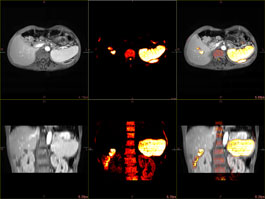

The PET/CT Fusion protocol provides flexible and simple image overlay analysis. Standard Uptake Value calculations are enabled with ROIs and VOIs.